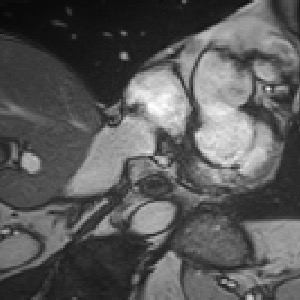

Transformers, the default model of choices in natural language processing, have drawn scant attention from the medical imaging community. Given the ability to exploit long-term dependencies, transformers are promising to help atypical convolutional neural networks (convnets) to overcome its inherent shortcomings of spatial inductive bias. However, most of recently proposed transformer-based segmentation approaches simply treated transformers as assisted modules to help encode global context into convolutional representations without investigating how to optimally combine self-attention (i.e., the core of transformers) with convolution. To address this issue, in this paper, we introduce nnFormer (i.e., Not-aNother transFormer), a powerful segmentation model with an interleaved architecture based on empirical combination of self-attention and convolution. In practice, nnFormer learns volumetric representations from 3D local volumes. Compared to the naive voxel-level self-attention implementation, such volume-based operations help to reduce the computational complexity by approximate 98% and 99.5% on Synapse and ACDC datasets, respectively. In comparison to prior-art network configurations, nnFormer achieves tremendous improvements over previous transformer-based methods on two commonly used datasets Synapse and ACDC. For instance, nnFormer outperforms Swin-UNet by over 7 percents on Synapse. Even when compared to nnUNet, currently the best performing fully-convolutional medical segmentation network, nnFormer still provides slightly better performance on Synapse and ACDC.